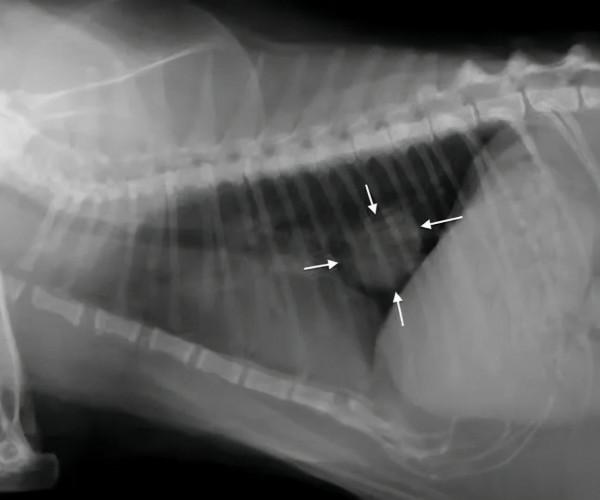

這是一隻患有肺癌的貓咪,這隻貓咪被證實經常處於二手菸的環境中。